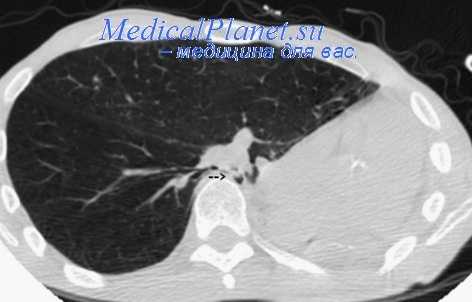

Резекция легкого (пневмонэктомия). Отсутствие динамики на фоне проводимой химиотерапии является основанием для решения вопроса о хирургическом вмешательстве. Это решается хирургом с участием фтизиатра, рентгенолога и бронхолога. Операции, как правило, должны производиться в фазу ремиссии.

Резекции легких бывают различными по объему. Чаще применяют экономные резекции (сегментэктомия, клиновидная, плоскостная). Еще более экономной является «высокоточная» резекция конгломерата очагов, туберкулемы или каверны с небольшим слоем неизмененной легочной ткани (Ю. М. Репин). Лобэктомии, билобэктомии (удаление одной или двух долей легкого) производят при тяжелых и распространенных процессах (кавернозный, фиброзно-кавернозный туберкулез).

Лобэктомии могут производиться при крупных, конгломератных туберкулемах и при циррозе доли. Если оставшаяся часть легкого недостаточна для заполнения плевральной полости, дополнительно накладывают ПП или производят 3—4-ю реберную торакопластику.

Пневмонэктомии являются вынужденными операциями при односторонних поражениях у больных фиброзно-кавернозным туберкулезом.